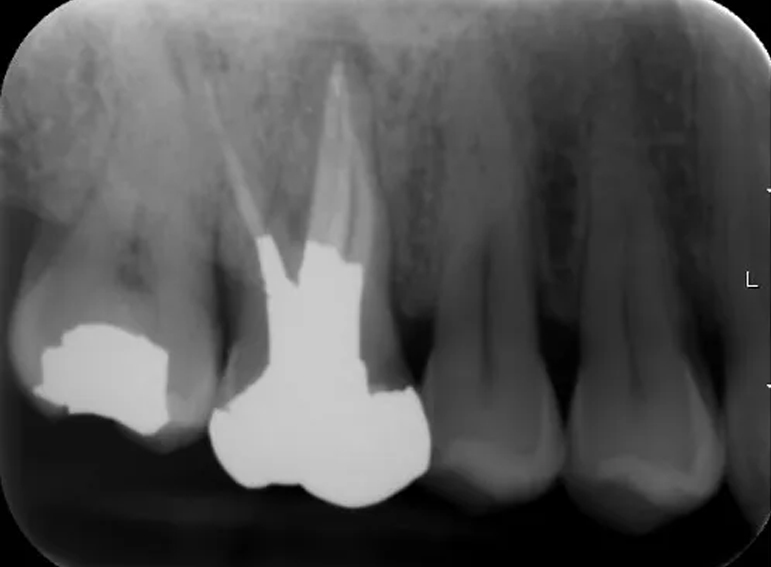

Removal of silver points and endodontic revision of a molar.